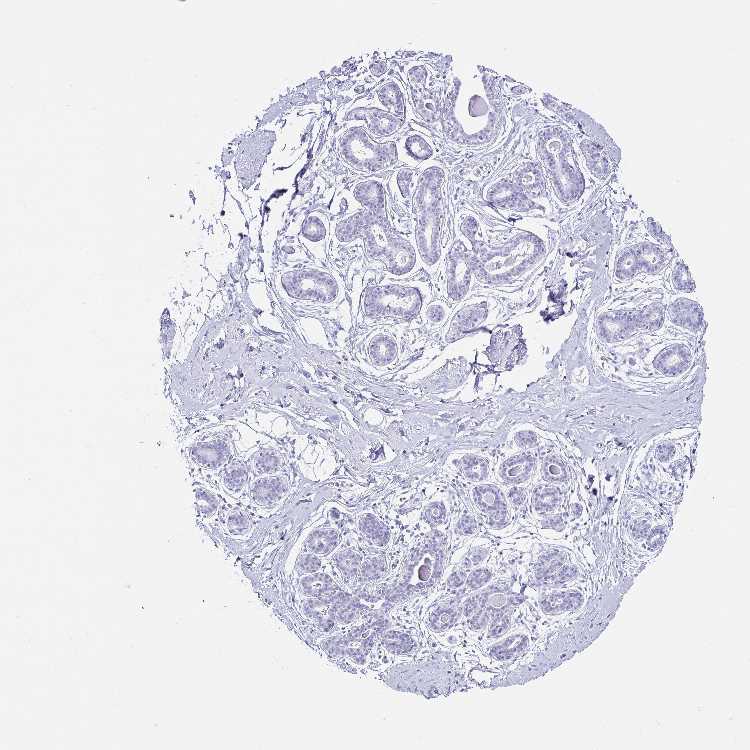

TISSUE PRIMARY DATA BREAST Show tissue menu

Breast

BREAST - Antibody stainingi

Antibody staining in the annotated cell types in the current human tissue is reported as not detected, low, medium, or high, based on conventional immunohistochemistry profiling in selected tissues. This score is based on the combination of the staining intensity and fraction of stained cells.

Each image is clickable and will lead to virtual microscopy that enables deeper exploration of all samples and also displays staining intensity scores, fraction scores and subcellular localization as well as patient and tissue information for each sample.

Antibody HPA062915

Adipocytes Not detected

Glandular cells Not detected

Myoepithelial cells Not detected